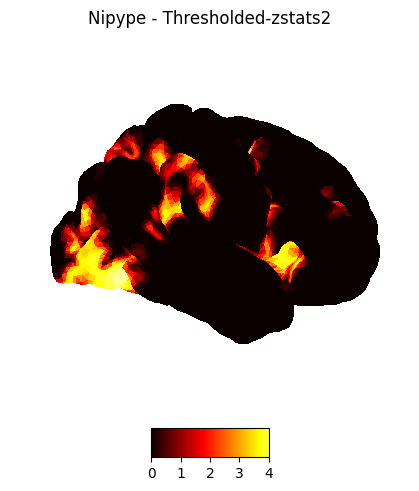

plotting.plot_img_on_surf(nipype_cope2,

views=['lateral'],

hemispheres=['right'],

title="Nipype - Thresholded-zstats2",

cmap = 'hot', colorbar=True)

plotting.show()

plotting.plot_img_on_surf(nipype_cope3,